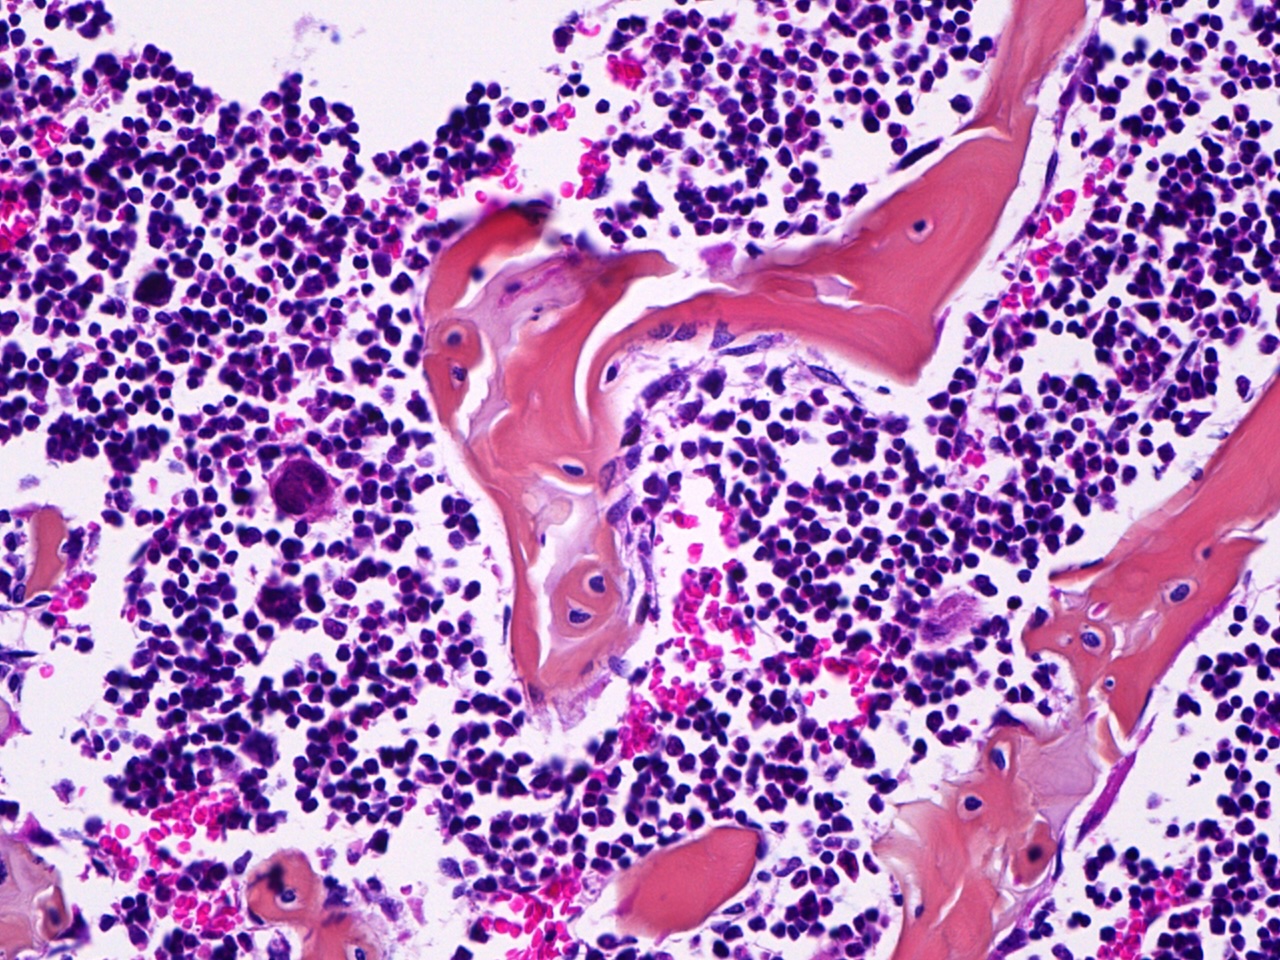

The MD Anderson Bone Histomorphometry Core Laboratory provides histomorphometric analyses of non-decalcified bone specimens. Bone specimens are processed for histology and can be stained for static and dynamic histomorphometric analyses (Osteomeasure or the Bioquant Osteo II system). The core can provides slides, data, training

Research Histology Core Lab: Bone Processing, Embedding and Sectioning

Bone Histomorphometry Core: Staining and Analysis